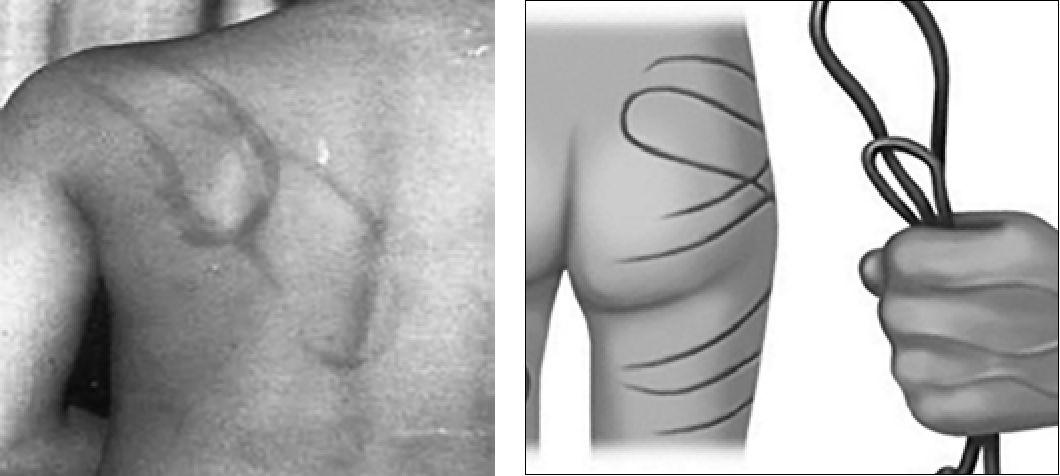

Кровоподтеки различной давности могут свидетельствовать о систематическом избиении ребенка (рис. 1).

Рис. 1. Следы физического насилия

Странгуляционные борозды на руках и ногах, иногда с осаднением, указывают на связывание ребенка. Наличие переломов, особенно нескольких, различной давности, отсутствие связи и/или недостаточно разумное объяснение возникновения травмы также служат основанием для подозрения в насилии над ребенком.

Наиболее частые варианты переломов вследствие жестокого обращения - переломы ребер, метафиза костей в результате тряски за конечность, акромиального отростка лопатки, грудины, стоп, остистых отростков и тел позвонков, множественные переломы черепа (рис. 2).

Рис. 2. Множественные переломы вследствие жестокого обращения с детьми